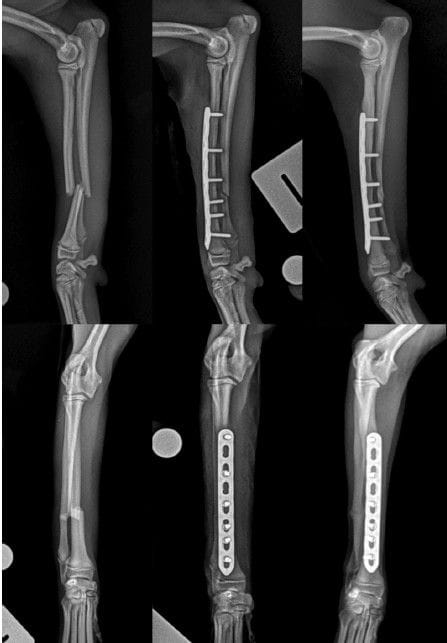

Preoperative (left), immediate postoperative (centre), and 8-

week postoperative radiographs demonstrating a diaphyseal, transverse

fracture of the left radius and ulna repaired with an 8-hole 1.5-

mm dynamic locking plate and subsequent fracture union in the

radius and ulna. Interfragmentary compression was compatible with

the fracture configuration and achieved through dynamic plate

compression.